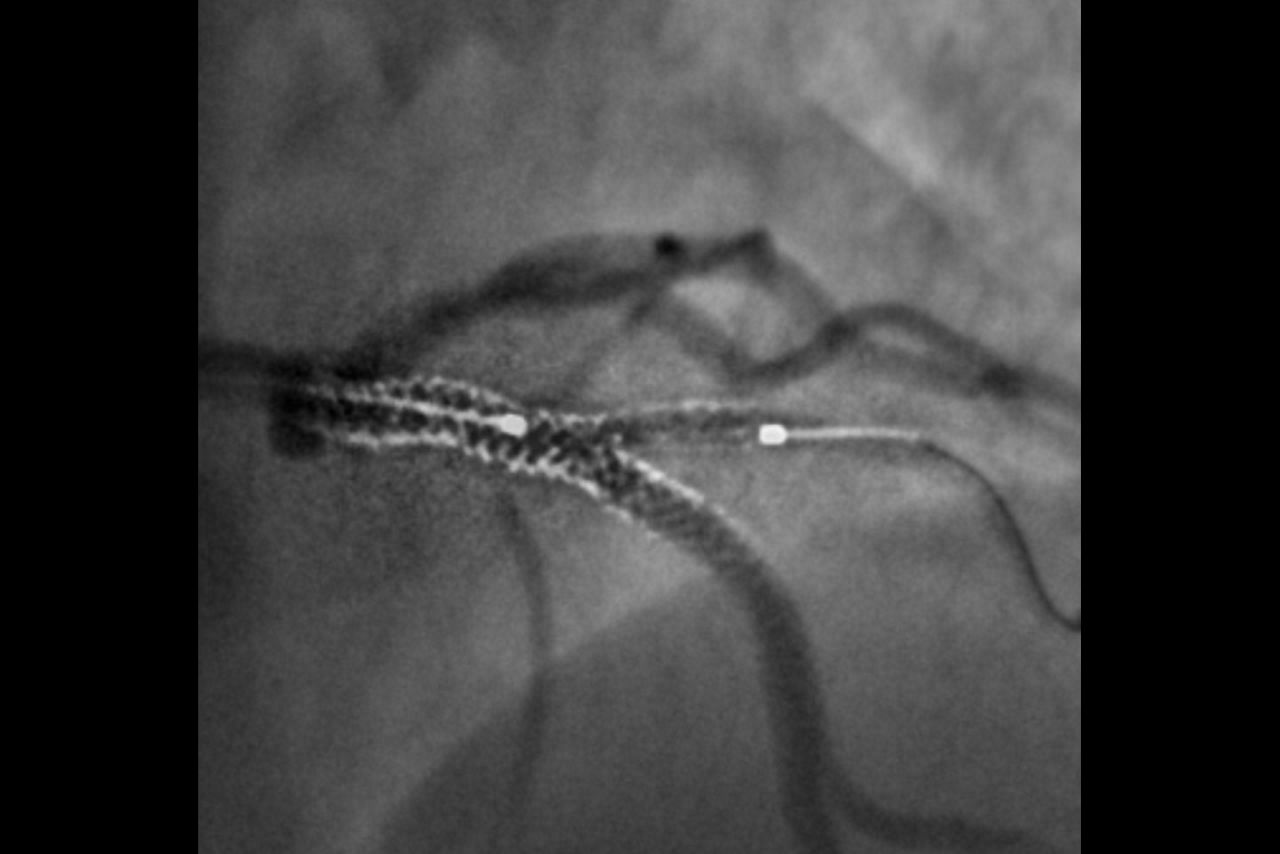

Guide

Augmented 2D image guidance

Help to increase positioning accuracy and confidence in multiple stent positioning.

Enhance the visibility of both stents in a bifurcation thanks to our improved StentViz algorithm.

Save time thanks to an automatic single acquisition workflow.

Improve anatomical visibility by up to 85%3,4 in moving arteries at the same radiation dose.